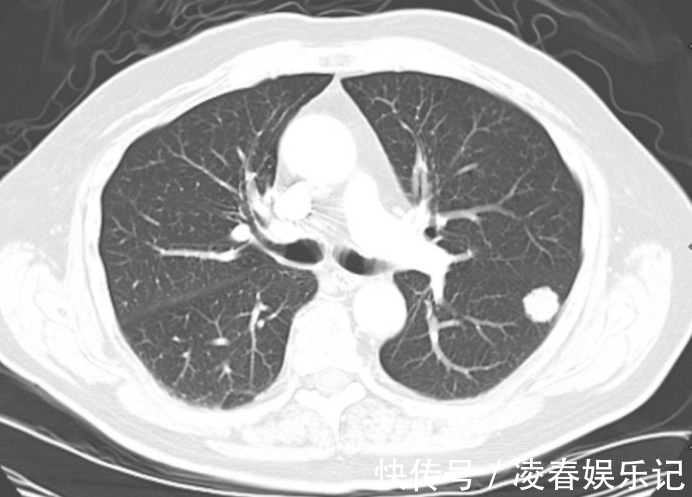

去年检查的时候就查出肺结节的问题,听到自己肺内长了东西,这吓坏了他,当即表示要戒烟,医生说戒烟是最好的,看了胡先生的检查单,医生说道,这个肺结节大概率是良性结节,癌变的可能性非常低,但是胡先生很害怕,整日里胆战心惊的。肺结节这种疾病近些年来变得越来越普遍,然而多数肺结节是良性结节,其中恶化的比例不到5%,因此即使查出肺结节的问题,也不再整天怨天尤人,避免过度恐慌。生活中多注意,慢慢结节是会消散的。

医生叹息:结节若是这3种,劝你放一百个心1、结节直径小于5毫米结节直径小于5毫米,这属于小结节,其中良性的概率高达95%,但是同时要注意若是结节直径超过1厘米,要尽快前往医院进行检查,同时确定下一步。2、异常结节形态清晰若是肺内结节边界清晰,没有毛刺,密度均匀,这大概率是良性结节,因此不必过于惊慌。

3、没有出现胸膜牵拉问题若是身体出现胸膜牵拉的问题,建议做进一步的穿刺活检,但是若是没有这种情况,不必过于惊慌。4、结节稳定若是结节长时间稳定,没有增大的趋势,说明结节属于良性结节。